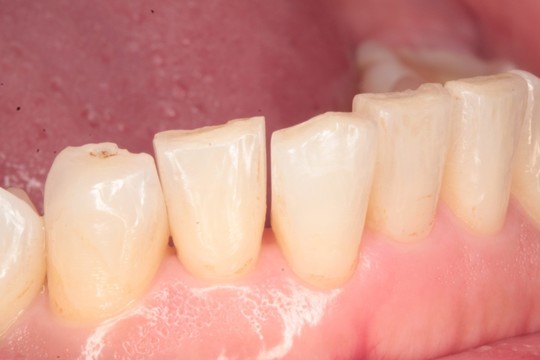

②IPRとは?

動画のようにIPRとは、薄く歯間を削り、スペースを得る方法です(1か所最大0.5㎜)。きちんと処理をすれば、痛みも害も出ません。むしろ、歯が強化されて虫歯になりにくくなる、という研究データすらあります。

IPR